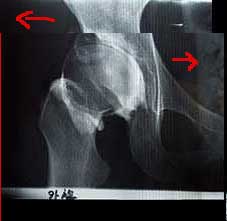

右の股関節X線です。赤い線のところで骨盤を二つに切ります。ノミやノコギリ?を使うようです。

そして切った部分を左右にずらし、足りない”かぶり”を人工的に大きくする。